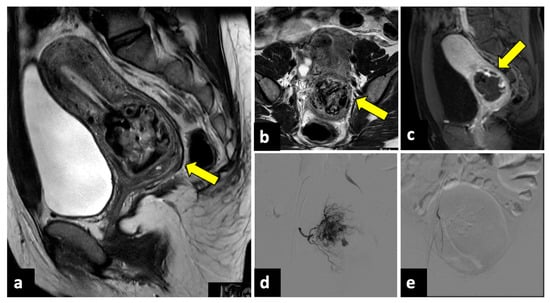

Red degeneration primarily occurs secondary to the rupture of intralesional arteries or venous thrombosis, leading to haemorrhagic infarction of leiomyomas. This condition usually manifests with APP, fever, and nausea. Upon US and CT imaging, red degenerated fibroids may appear as large, inhomogeneous, and well-circumscribed intramural masses, with cystic areas and an absence of Doppler signal/flow in infarction areas. MRI examinations may demonstrate a peripheral high-intensity rim on T1-weighted images due to the T1 shortening effects of the methaemoglobin of blood products confined to the thrombosed and dilated vascular structures surrounding the leiomyoma. In gadolinium-enhanced fat-suppressed T1-weighted sequences, red degenerated leiomyomas do not show contrast enhancement (Figure 6) [47,49].

Figure 6.

Red degenerated leiomyoma in a thirty-one-year-old woman with abdominal pain and vaginal bleeding after a miscarriage. T2-weighted imaging (a) showed an enlarged uterus with degenerated intramural and pedunculated leiomyomas with inhomogeneous intensity (yellow arrow). On T1-weighted sequence (b), a peripheral hyperintense rim surrounding the lesion’s central area of lower signal intensity (red arrows), typical of red degeneration of leiomyomas, is observed. No intralesional enhancement was seen after intravenous contrast injection ((c), blue arrows).